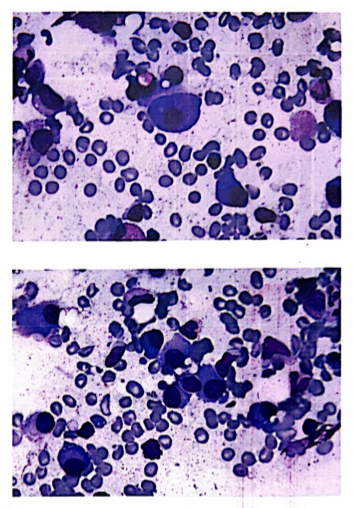

骨髓涂片:全片瘤细胞异常增生,占43.5%,该类细胞外形不规则,胞浆较丰富,兰色或火焰色,核圆形,偏位,核染色质较细致,可见核仁1~2个,可见双核型瘤细胞。

骨髓活检:骨髓增生较活跃(60%),异常浆细胞增多(40%),胞体中等大,胞浆丰富,胞核圆形或略不规则,染色质粗,粒红系各阶段细胞可见,以中幼及以下阶段细胞为主,巨核细胞数量及形态大致正常,分叶核为主:少量淋巴细胞散在分布。网状纤维染色(MF-1级)。

骨髓涂片:浆细胞明显增生,考虑多发性骨髓瘤。